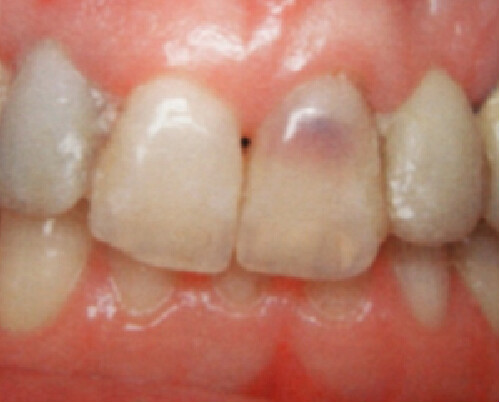

An internal resorption pink spot was historically referred to as the “pink tooth of Mummery,” named for the anatomist who described the condition. Like an ECR lesion, in this type of resorption, patients are typically asymptomatic, and the lesion is only noted either by its pink color that patients may notice prior to their visit or from routine radiographs.

In order for this type of resorption to occur, some type of damage had to take place inside the predentin layer, with inflammation present. Predisposing factors for this type of resorption include caries, trauma, restorative procedures, and heat. Vital pulp tissue is needed for this type of resorptive process to continue.

If the lesion becomes significant in size, necrosis of the pulp usually occurs, at which point the patient will begin to have typical pulpitis-related symptoms. Since the vascular tissue becomes necrotic, the tooth’s color may appear darker or gray with discoloration. Root canal therapy will resolve this type of resorptive process. As long as the process has not resorbed a significant portion of the tooth, prognosis is favorable. Repairs can be made with bioceramics, even in situations where the lesion has perforated to the external surface.